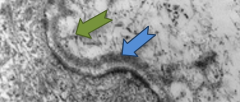

矽烷醇

是含有豐富羥基作用的有機矽衍生物,透過與不同的根基結合,給與其複合物穩定性及不同的特性。矽自然存在於人體皮膚中,尤其是結締組織的重要結構元素。矽含量隨著年齡不斷減少,透過矽烷醇補充矽元素來改善微循環,使整體皮膚結構健康和年輕。